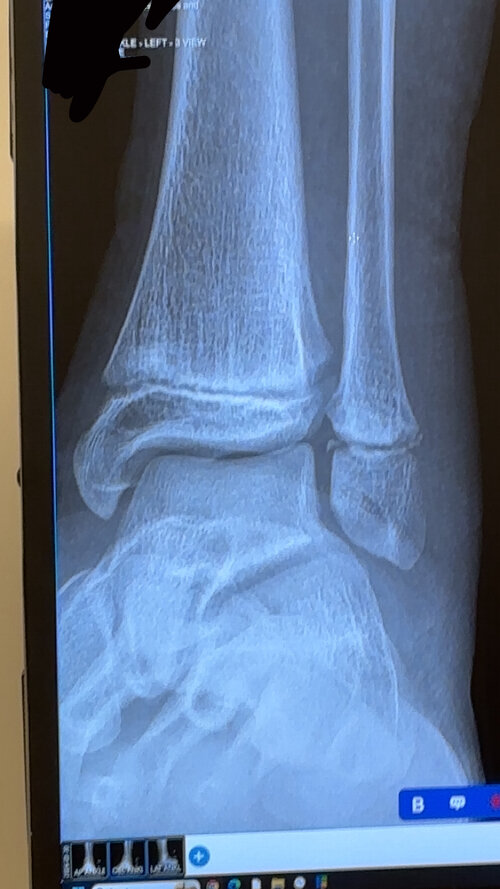

I fractured my ankle a few weeks ago, obviously I know to properly check growth plates you need a hand X-ray but this can do. Still waiting on my growth spurts and puberty

• IMG_8095.jpeg

IMG_8095.jpeg

453.2 KB · Views: 0